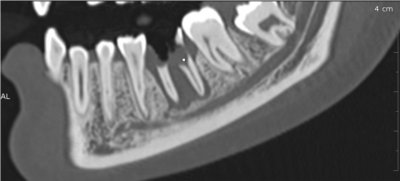

Les nouvelles générations de scanner permettent de faire une acquisition d’un volume global d’une partie du corps et de travailler à l’intérieur de ce volume en isolant une structure anatomique donnée et de l’explorer dans tous les plans de l’espace.

Grace à la technique de seuillage il est possible de dissocier progressivement les dents des structures osseuses environnantes dans le volume donné.